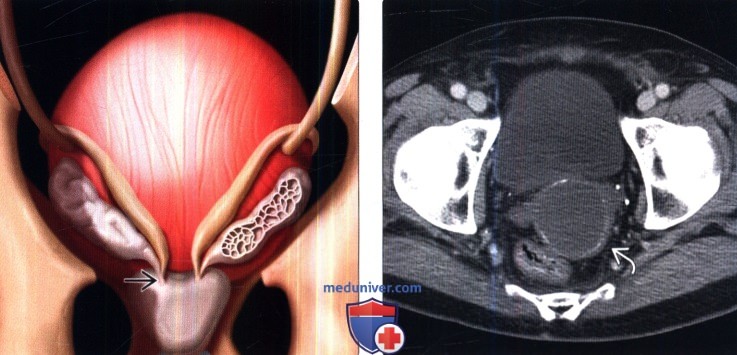

КТ-исследование абсцесса малого таза: Визуализация и диагностика